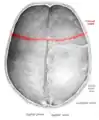

Superior view of the skull. ("Coronal suture" in red.)

The coronal suture is a dense, fibrous connective tissue joint that separates the two parietal bones from the frontal bone of the skull.

The coronal suture lies between the paired parietal bones and the frontal bone of the skull.[1] It runs from the pterion on each side.